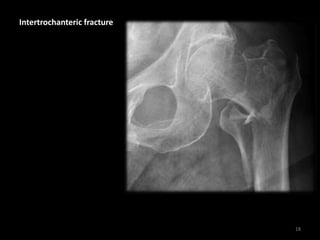

Intertrochanteric fracture

• A fracture line runs

between the

trochanters

• There is

comminution with

separation of the

lesser trochanter

• Note the fracture

does not involve the

femoral neck

19